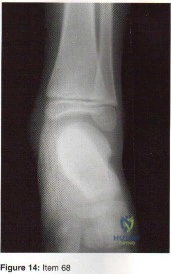

- widening and shortening of the heel.

- weakness of the gastrocnemius-soleus complex.

- anterior impingement from a horizontal talus.

- unrecognized compartment syndrome of the foot.

- degenerative arthritis of the tibiotalar joint.